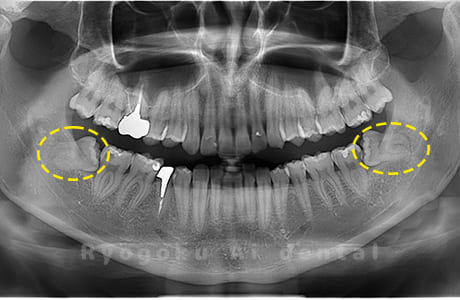

- 上顎の親知らず、下顎の水平埋伏の親知らず

- 治療内容

- 上顎の親知らず、下顎の水平埋伏の親知らずを抜歯したケースです。

<リスク・副作用>

手術後は痛み、腫れ、痺れなどの副作用が生じる場合があります。